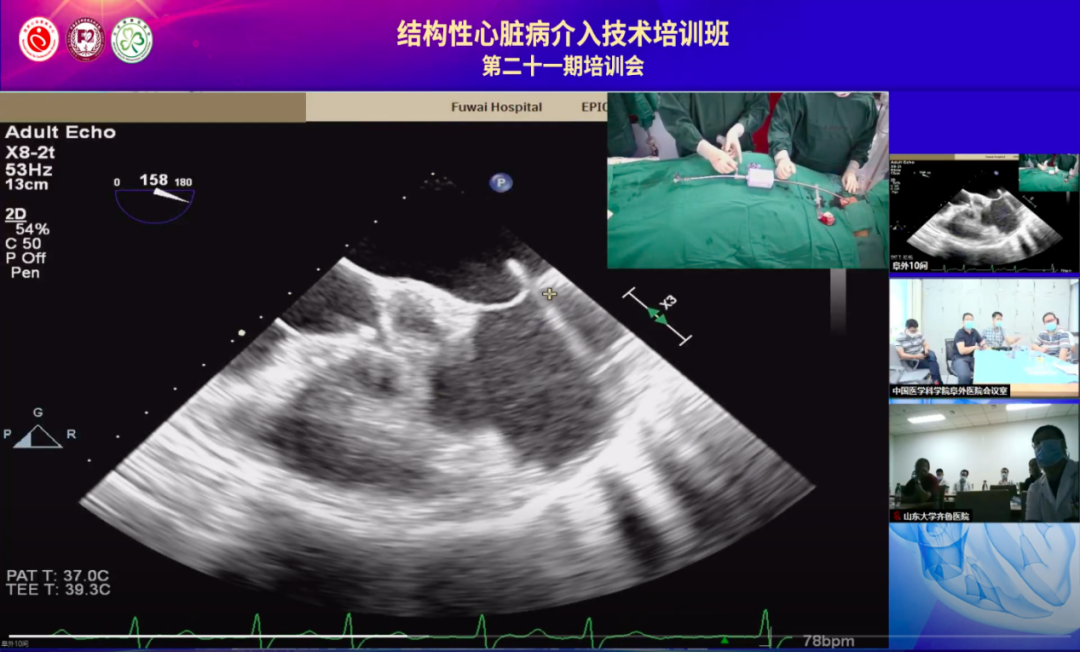

手术团队使用MitraClip独特的三层双调弯导管,经股静脉穿刺,在食道超声引导下完成房间隔穿刺,由于患者心脏转位明显,超声反复确定位置,确保穿刺位置距离二尖瓣环水平的高度不低于40mm。

经食道超声确定穿刺部位